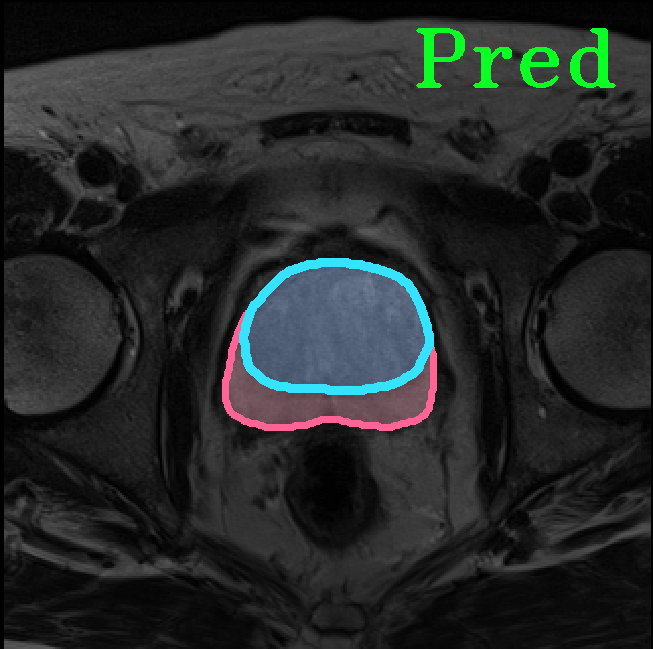

TransFuse is evaluated on both 2D and 3D datasets to demonstrate the effectiveness. As different medical image segmentation tasks serve different diagnosis or operative purposes, we follow the commonly used evaluation metrics for each of the segmentation tasks to quantitatively analyze the results. Selected visualization results of TransFuse-S are shown in Fig. 2.

Results of Prostate Segmentation. We compare TransFuse-S with nnU-Net [12], which ranked 1st in the prostate segmentation challenge [22]. We follow the same preprocessing, training as well as evaluation schemes of the publicly available nnU-Net framework333https://github.com/MIC-DKFZ/nnUNet and report the 5-fold cross validation results in Tab. 6. We can find that TransFuse-S surpasses nnUNet-2d by a large margin (+4.2%) in terms of the mean dice score. Compared to nnUNet-3d, TransFuse-S not only achieves better performance, but also reduces the number of parameters by 41% and increases the throughput by 50% (on GTX1080).

| Prostate Segmentation | |||

|

|

|

|